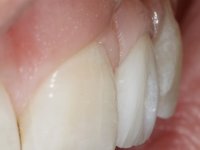

Female patient, 24 years of age, non-smoker. The clinical situation resulted from an orthodontic treatment performed with the intention of resolving a problem of unilateral agenesis of the left lateral incisor. After orthodontic correction, an implant was placed at the site of tooth 2.2. During the period of osseointegration the patient used a removable orthodontic appliance with a prosthetic tooth. Upon assessment of the situation, I registered the following aesthetic conditions:

1. The cervical level of the teeth 1.3.1.2 and 1.1 are at a more incisal level than the teeth 2.1 and 2.3.

2. The distal papillae of 2.1 and mesial of 2.3 disappeared.

3. Slight radicular exposure in distal 2.1 and mesial 2.3.

4. The edentulous space corresponding to the high and narrow 2.2.

5. Tooth 1.2 with microdontia and rolled.